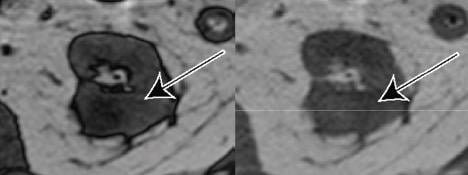

64-Year-Old Man With Clear Cell Likelihood Score (ccLS) 5 Renal Masses. Coronal T2-weighted single shot fast spin echo and coronal T1-weighted fat-saturated spoiled gradient echo acquired during corticomedullary phase—ccLS5 lesion outlined red for clarity.

Extracted from clinical reports, “the ccLS scores the likelihood that the small renal mass represents clear cell renal cell carcinoma, from 1 (very unlikely) to 5 (very likely),” explained corresponding author Ivan Pedrosa from the University of Texas Southwestern Medical Center at Dallas. “Small renal masses with lower ccLS may be considered for active surveillance, whereas small renal masses with higher ccLS may warrant earlier intervention.”